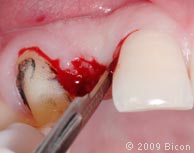

26. Для раскрытия верхнего бокового правого резца сделан надрез.